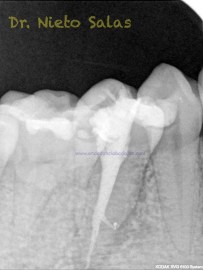

Nos llega a la clínica  este 4.5 con necrosis y periodontitis apical. la instrumentación se realizó con técnica de crown-down con limas K3 (SybronEndo) y la obturación con la técnica de ola continua de Buchanan, el tiempo de trabajo (para mi bastante importante) sobre 70-90 min.

Pero no todo se va a dejar al «poder de la irrigación»,  es muy importante la biomecánica, y la intuición para poder instrumentar esos pequeños conductos laterales que es muchas ocasiones nos dan problemas. Así, pues, os pongo un par de casos que con ayuda de esta «intuición» pudimos hacer un buen tratamiento.

Presentaban un sondaje normal, y sospechamos de que podía tratarse de lesiones por conductos laterales.

Una vez que hemos desbridado biomecánicamente con limas de muy pequeño diámetro, obturamos: